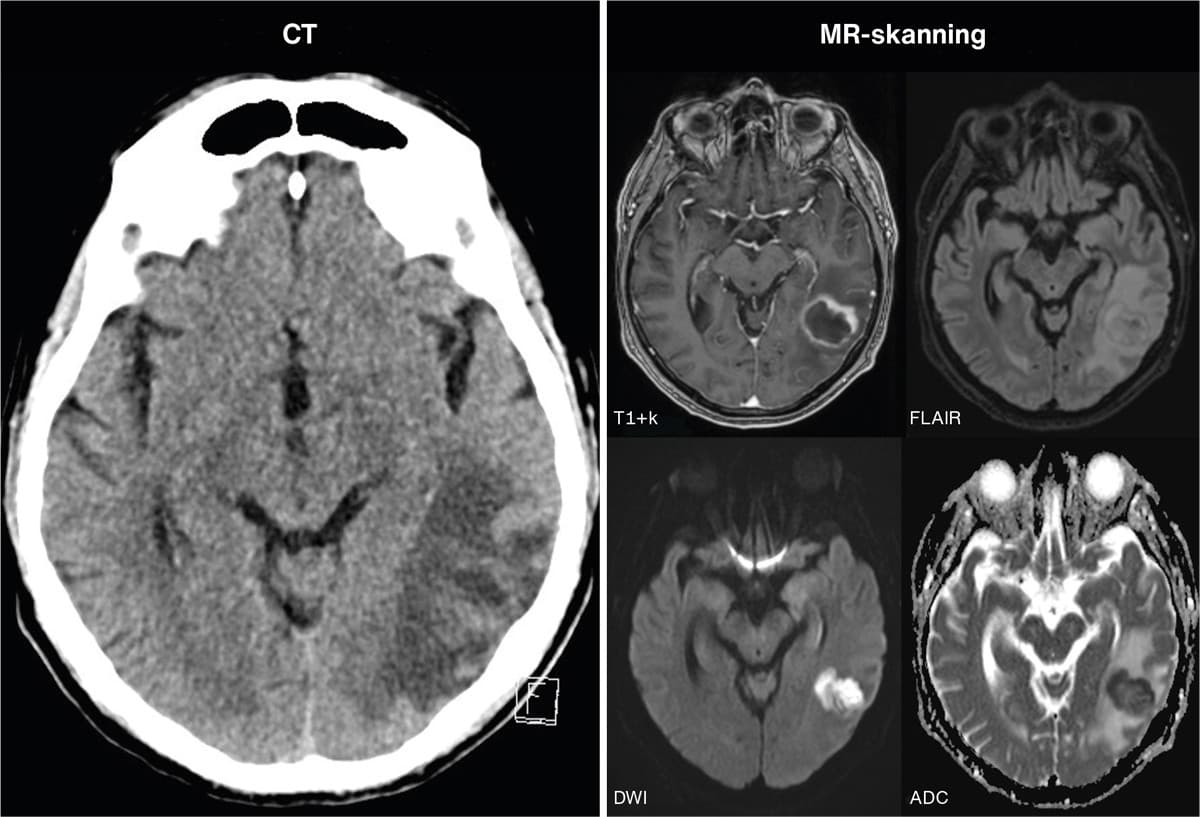

En 79-årig immunkompetent mand blev indlagt med få ugers varende impressiv afasi og konfusion. En CT af cerebrum viste en venstresidig temporo-occipital proces med omgivende ødem. Initialt var der mistanke om hjernemetastase eller glioblastom. Der blev uden effekt på symptomerne givet højdosisprednisolon. Pga. tiltagende febrilia, samt stigende CRP-niveau og neutrofile leukocytter tog man blod- og urindyrkninger, og der blev påbegyndt behandling med piperacillin/tazobactam for infektion med ukendt fokus. En supplerende MR-skanning af cerebrum med i.v. kontrast og diffusionssekvenser viste cerebral absces. Antibiotikabehandlingen blev skiftet til ceftriaxon og metronidazol (empirisk standardbehandling for cerebral absces [1]), og abscessen blev dræneret akut. Abscesmaterialet blev dyrket, og der forekom vækst af Streptococcus anginosus-gruppen, der bl.a. er kendt for at danne intracerebrale abscesser [2]. Bloddyrkningerne udkom uden betydende fund. Patienten responderede godt på behandlingen.

Cerebrale abscesser kan klinisk og paraklinisk ligne andre sygdomme, herunder malignitet. Supplerende billeddiagnostik med MR-skanning kan støtte diagnosen. Bloddyrkninger kan være negative. Akut drænage er både terapeutisk og af stor værdi for mikrobiologisk diagnostik.